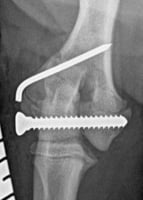

The surgical wound is then closed in two layers. The tarsal suture brings together the “tarsal” plates (deeper layer) of both eyelid margins using a far-near-across-near-far loop technique. This is followed by suturing the subconjunctival layers with 6-0 absorbable suture material using a simple interrupted vertical U suture or a continuous suture pattern. A figure-of-eight suture, bringing together the free eyelid margins, is performed by entering the skin of one eyelid approximately 2mm from the eyelid margin and 1mm from the wound, directed obliquely to the opposite side of the surgical wound.

The needle then enters the contralateral eyelid wound and exits approximately two meibomian gland openings away from the wound margin. This movement is then repeated in reverse on the other side of the wound, entering approximately two meibomian gland openings from the wound margin and directed obliquely to the opposite side, exiting through the eyelid skin 2mm from the free margin and 1mm from the wound margin (Figure 3). All entry and exit points must be equidistant from the wound margins and symmetrical on both sides of the wound. The remainder of the skin incision (involving the skin and orbicularis muscle) is sutured with 6-0 absorbable or non-absorbable suture material using a simple interrupted pattern until the wound is fully closed.